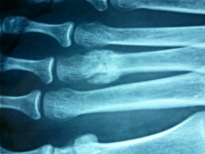

Il s’agit d’une fracture progressive d’un os, entraînant une douleur croissante lors de l’appui.

Elle peut être partielle ou atteindre toute la largeur de l'os.

Elle est due à un excès de contraintes au niveau de l’os et survient sans traumatisme important après un surmenage mécanique du pied.

Les os longs du médio-pied (les métatarsiens) sont le plus souvent atteints car ils constituent le sommet de la charpente osseuse du pied.